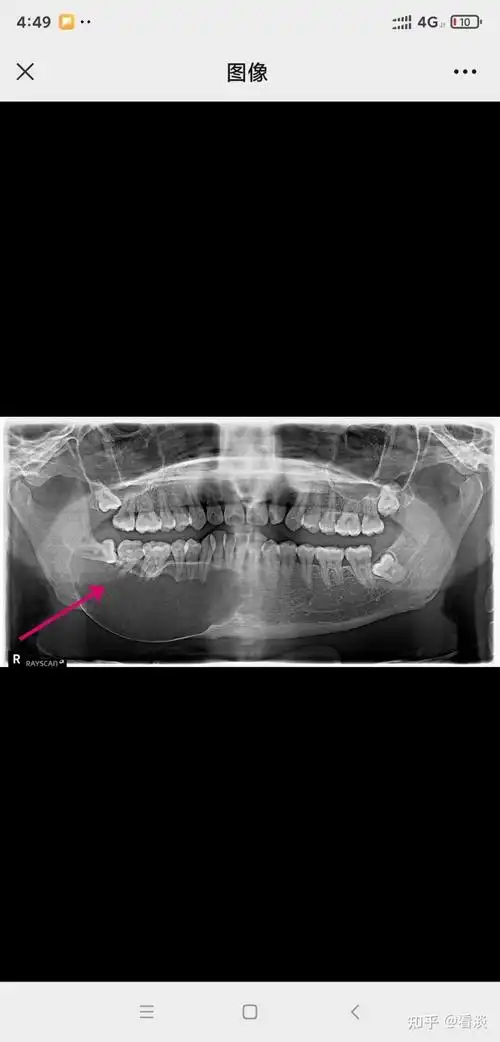

下颌骨囊肿伴感染